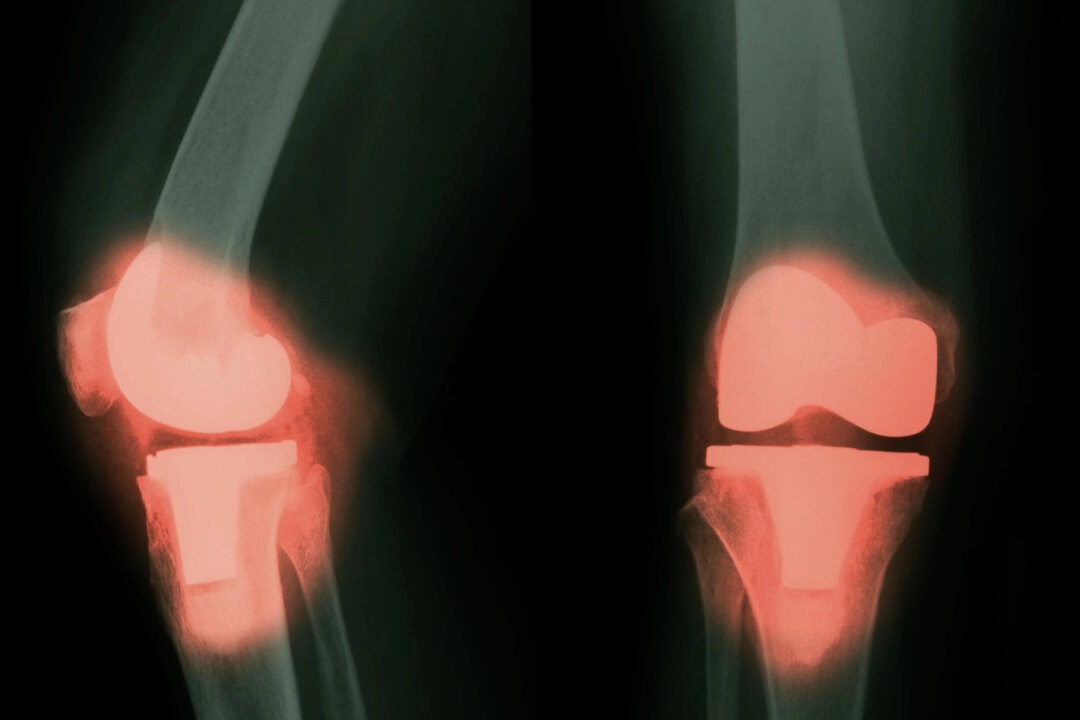

【大紀元2025年04月23日訊】(George Citroner報導/大紀元記者王月編輯)一項新研究發現,有些接受過常規大型關節置換手術的患者,其血液、大腦和脊髓液中的某些金屬含量會升高,這引發了人們的擔憂:體內金屬含量的升高是否會對神經系統造成長期的不良反應。

在美國,每年大約進行79萬例全膝關節置換手術和54.4萬例髖關節置換手術,預計隨著人口老齡化,這些數字還將繼續上升。

一項名為「NeuroWear」的試點研究項目,其成果最近發表在了《JAMA Network Open》期刊上,該研究對比評估了103名植入關節假體者與108名未植入者的情況。

研究發現,植入假體的患者其血液和腦脊液(CSF)中的金屬濃度更高,這表明來自假體的金屬——尤其是鈷——可能會進入中樞神經系統。

在腦脊液中,植入組的鈷濃度為每升0.03微克,而對照組(未植入者)為每升0.02微克。

除了鈷之外,植入假體的患者,其血液中還出現了更高濃度的鉻、鈦、鈮和鋯,其中一些金屬也在他們的腦脊液中被檢測到。值得注意的是,植入了鈷-鉻-鉬合金的患者,其體內的金屬含量會更高。

目前,鈦和鈷-鉻合金是製造假體關節最常用的金屬材料。鈷-鉻-鉬合金以其強度高、耐用性強和抗腐蝕能力強而聞名,因此被廣泛用於金屬關節置換中,特別是在髖關節和膝關節假體中。不過,這些關節也可能包含陶瓷材料,像是氧化鋁和氧化鋯。在某些組件中,特別是髖關節假肢中,這些陶瓷材料可以提高耐磨性和生物相容性。